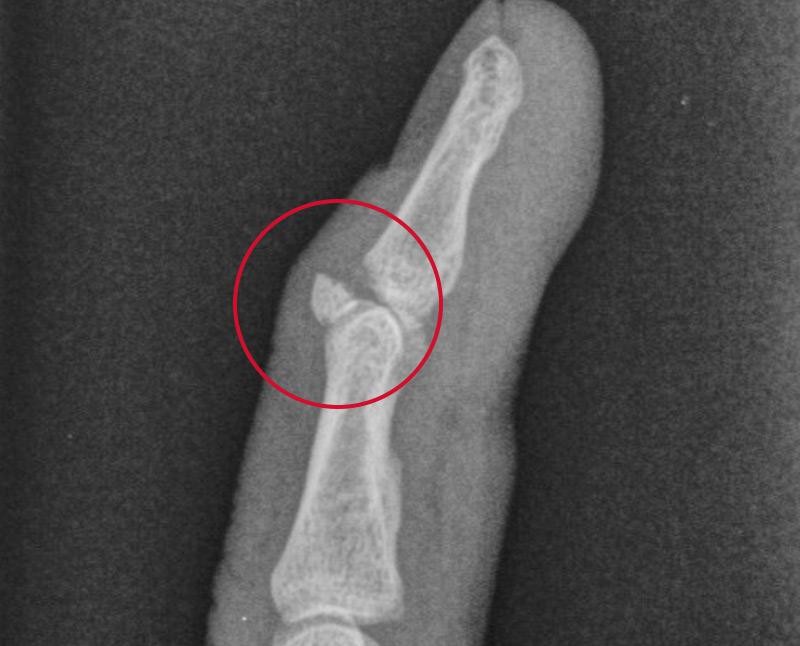

An avulsion fracture is where a small piece of bone attached to a tendon or ligament gets pulled away from the main part of the bone. Ligaments hold your bones, joints and organs in place while tendons connect muscles and bones. In an avulsion fracture, your bone moves one way and your tendon or ligament moves in the opposite direction with a broken chunk of bone in tow. This most often happens when you suddenly change direction.

- X-rays to look at your bones and joints.

- Computed tomography (CT scan) to look at your soft tissues and organs and get a more precise view of your bones and joints. This is performed if X-rays are unclear.